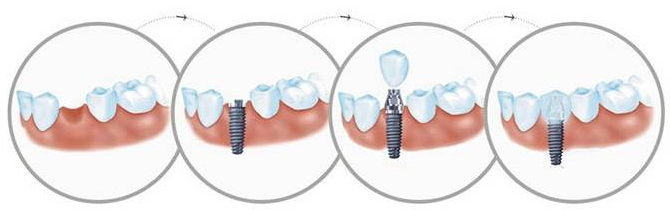

ЫцзХШЫУЧПкЧЛБЃНЁвтЪЖЕФдіЧПЃЌДѓЖрЪ§ШЫЖМжЊЕРбРГнАЮГ§КѓгІЕНвНдКЯтбРЃЌЕЋЪЧЪВУДЪБМфЯтбРКУФи?

вЛАуАЮбРКѓ3ИідТзѓгвПЩвдЯтбРЁЃетЪЧвђЮЊАЮбРКѓЩЫПкЕФЭъШЋгњКЯашвЊСНИіЙ§ГЬЃКШэзщжЏ(бРіИ)ЕФгњКЯаш7вЛ10ЬьЃЛЖјАЮбРКѓЕФбРВлЙЧдђашвЊ3ИідТзѓгвЃЌВХФмЭъШЋаЮГЩЙЧзщжЏЁЃ3ИідТжаЃЌбРВлЙЧдкАЮбРКѓЕФЧА2ИідТФкЮќЪеБШНЯУїЯдЃЌвдКѓМѕТ§ЃЌж№НЅЮШЖЈЁЃЯтбРзюКУвЊЕШЕНбРВлЙЧЭъШЋгњКЯжЎКѓЃЌАЮбРЧјЕФбРВлЙЧДІгкЮШЖЈЪБЃЌМД3ИідТзѓгвЁЃЁЗЁЗЁЗЭЦМідФЖСЃКМДПЬжжжВбРашвЊТњзуЪВУДЬѕМўЃП

ШчЙћЙ§дчЯтбРЃЌАЮбРЧјбРВлЙЧЛЙДІгкУїЯдЮќЪеЪБЦкЃЌжТЪЙМйбРЕзВПгыбРВлсе(бРВлсеАќРЈбРАЮГ§КѓжмЮЇЕФбРВлЭЛгыЦфЩЯИВИЧЕФ№ЄФЄЃЌЫзГЦ“бРДВ”бРВлсеБэУцЕФ№ЄФЄжТУмЁЂМсШЭЁЂИЛгаЕЏадЁЃбРВлсеПЩвджБНгЛђЭЈЙ§МйбРЛљЭаГаЕЃОзНРбЙСІЃЌгШЦфЪЧбРВлсеЖЅВПИќЪЪвЫГаЕЃЪЪЕБЕФОзНРбЙСІ)ВЛЬљКЯЃЌГіЯжМфЯЖЃЌдьГЩЪГЮяЕФВаСєЃЌЩѕжСМйбРЧЬЖЏКЭбЙЭДЃЌЧщПібЯжиепвЊжизіМйбРЁЃ

ШчЙћЙ§ЭэЯтбРЃЌШБбРЧјСНВрЕФЬьШЛбРЛсЯђШБбРМфЯЖЧуаБЃЌЪЙЕУШБЯЖБфеЃЌМгжЎЖдДљбРЩьГЄЃЌЪЙШБбРМфЯЖИпЖШБфЕЭЃЌЖМЛсИјМйбРЕФжЦзїДјРДРЇФбЁЃЕЋгавЛжжЧщПіР§ЭтЃЌШєЛМепвђЙЄзїашвЊМБгкаоИДЃЌПЩвддкАЮбРКѓМДЯтбРЃЌЕЋашвЊЖрДЮИДеяЁЃ